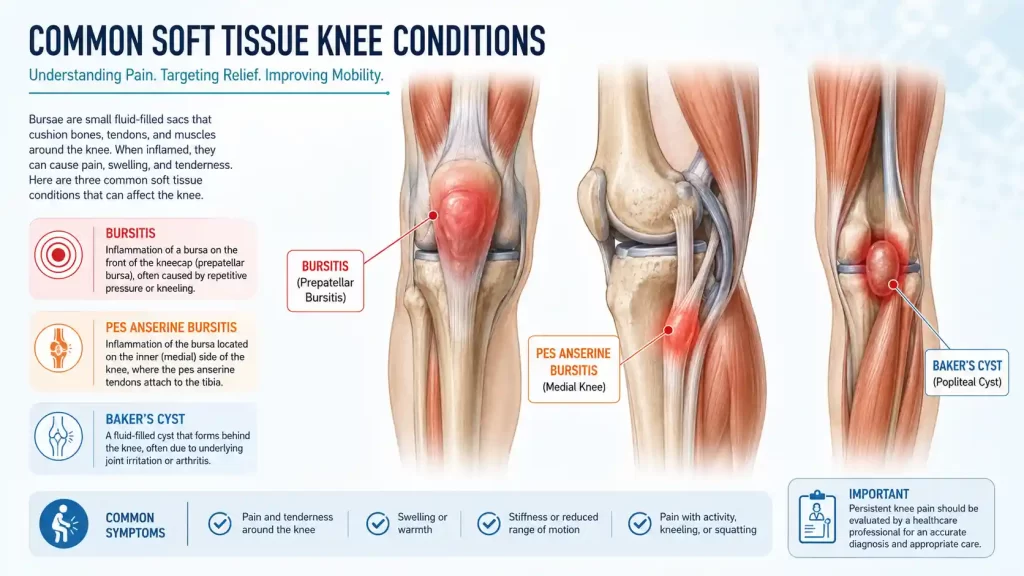

Bursae are small, fluid-filled sacs nature’s friction pads positioned between tendons, muscles, and bony prominences. The knee has over 13 bursae. When one becomes inflamed (bursitis), it produces localised pain, tenderness, and swelling that is distinct from intra-articular pathology.

Inflammation of the bursa in front of the patella caused by prolonged kneeling. Common in tilers, gardeners, and plumbers. The knee cap appears swollen, warm, and fluctuant. Usually responds to aspiration, padding, and a corticosteroid injection.

Often overlooked, this is inflammation of the bursa at the inner aspect of the upper shin — where the tendons of three muscles (sartorius, gracilis, semimembranosus) insert together, resembling a goose’s foot (pes anserine). It produces inner-knee pain worse at night and with stair climbing, commonly in overweight patients with OA. Ultrasound-guided injection with corticosteroid or PRP is highly effective and forms a core IBAP treatment.

A Baker’s cyst is not a primary pathology — it is a secondary symptom. When the knee joint produces excess synovial fluid (in response to OA, meniscal tears, or RA), the fluid is pushed into the popliteal fossa (back of the knee) through a one-way valve in the joint capsule, forming a cyst. Treating the underlying cause — and aspirating the cyst under ultrasound guidance — resolves the problem definitively.

Pes Anserine Bursitis is a frequently missed diagnosis — particularly in diabetic patients and those with knee OA. If you have medial knee pain that is worse at night, ask us to check specifically for this condition.

Caution: A ruptured Baker’s cyst can mimic a deep vein thrombosis (DVT) — causing sudden calf pain and swelling. Both conditions require urgent clinical assessment to distinguish them. IBAP Clinics uses ultrasound imaging to confirm the diagnosis at the point of care.